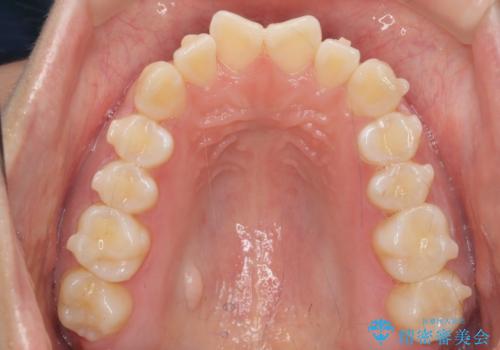

インビザライン モニター治療 前歯のねじれをまっすぐに

- 前歯のねじれを主訴に来院。

インビザラインの部分矯正コースではなく全体矯正コースをご希望でした。

前歯のねじれやがたつきだったため、モニター治療での低価格でのご提案が可能でした。

年齢が10代なこともあり、歯の動きは非常によく、リファインメントなしできれいに並びました。

下の前歯を少し削合して並べています。